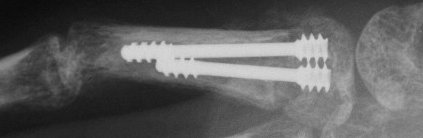

| Proximal phalanx fractures are a common problem with many treatment options. These images illustrate a technique of stabilization using intramedullary Herbert screws placed percutaneously through the base of the proximal phalanx. Provisional fixation is obtained with K wires which are replaced with Herbert screws, which simply follow the soft tissue path of the pin tract to the bone. Self tapping screws are not used in this technique, as the cutting threads catch on soft tissues. |

| A second case, five weeks after injury with early callus, treated with similar technique after percutaneous fracture mobilization with a small elevator. |